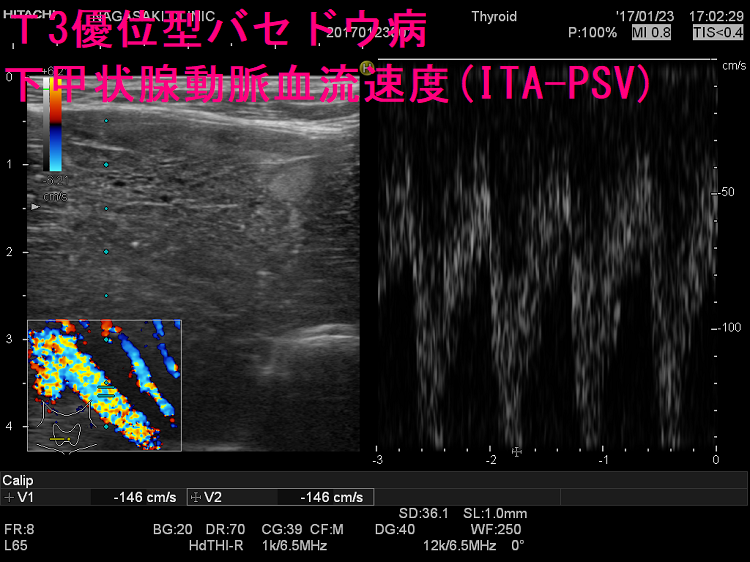

ケース① 下甲状腺動脈血流速度(ITA-PSV)は異常高値

T3優位型バセドウ病 超音波(エコー)画像 ドプラーモード:下甲状腺動脈血流速度(ITA-PSV)は異常高値です。

難治性T3優位型バセドウ病は若年女性に多く、甲状腺組織の2型脱ヨード酵素(DIO 2)活性が異常に高いため、FT4に比べFT3が著明高値になる。巨大甲状腺腫、TSH レセプター抗体(TRAb)異常高値、甲状腺超音波エコー検査で下甲状腺動脈は異常に太く、下甲状腺動脈血流速度ITA-PSVも異常高値。薬物治療抵抗性で、FT4正常化してもFT3は高値、再発繰り返す。I-131治療は1回で終わらず、甲状腺全摘出手術になる。服薬アドヒアランス不良は患者がメルカゾール・プロパジールを服用しない事。難治性バセドウ病と思って薬を増やしても、甲状腺ホルモンは下がらない。

- 甲状腺超音波(エコー)検査で、下甲状腺動脈が異常に太く、下甲状腺動脈血流速度(ITA-PSV)が異常高値